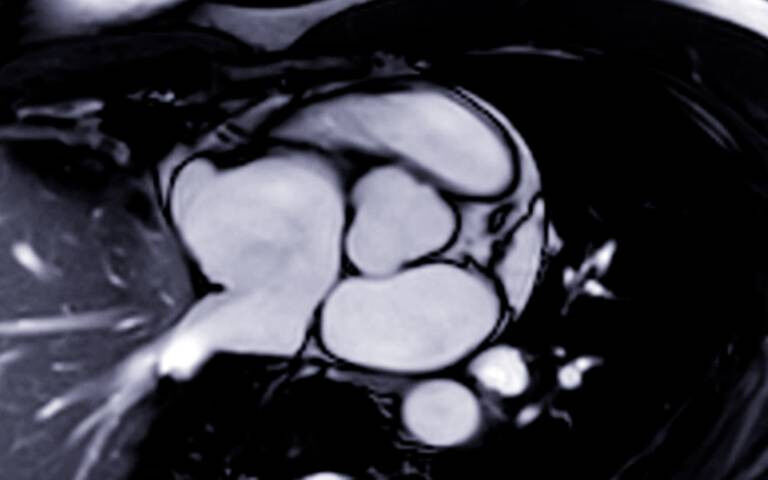

The new study, published in the journal JACC: Cardiovascular Imaging, found that MRI detected heart inflammation, scarring, and impaired function among carriers of a mutated LMNA gene whose hearts would have been classed as healthy according to more standard tests.

The team argued that this information from MRI - the gold standard of heart imaging - should be included in how disease risk is estimated and inform decisions about which patients should receive a heart transplant or an implantable defibrillator (a device that monitors the heartbeat and can deliver an electrical shock if a dangerous rhythm is detected).

Lead author Dr Cristian Topriceanu (UCL Institute of Cardiovascular Science) said: "Cardiac MRI picks up scarring of the heart tissue, inflammation and signs the heart muscle is not working as well as it should among carriers of an LMNA mutation who do not have more overt signs of disease and whose heart is pumping blood normally. These are signals that other tests such as an ECG or an echocardiogram would have missed.